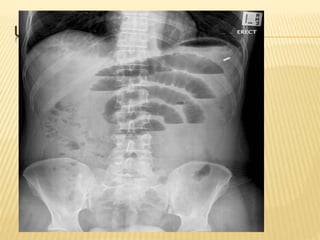

UPRIGHT ABD X-RAY

BOWEL OBSTRUCTION

 Abdominal x-ray series

 Flat, upright, and chest x-ray

 Air-fluid levels, dilated loops of

bowel

 Lack of gas in distal bowel and

rectum